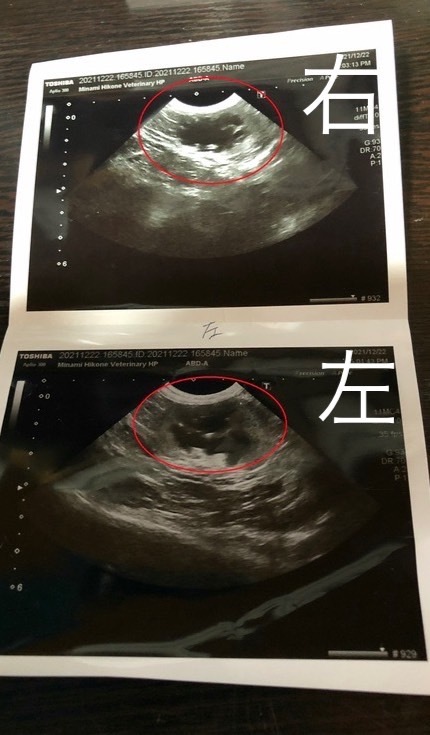

まずエコー検査で判明したことは、左右に一つずつある腎臓の1つ全くダメになっている。

そして残りのもう一つの腎臓にも結石(塊ではなく砂のような細かなもの)があり、それが尿管の入り口を塞いで腎臓が機能できず腎不全を起こしてしまっている状態でした。

↑初診時の検査結果です。